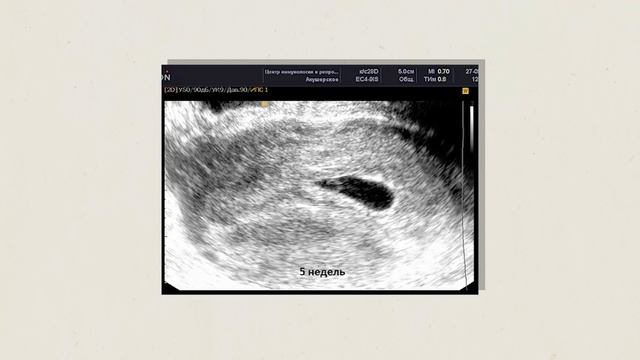

«Постоянно думаешь, как будут счастливы родители, когда ты подаришь им ребенка» — признается наша суррогатная мама Юлия ✨ Действительно, сурматеринство — одно из самых сложных решений, которое требует смелости, ответственности и безвозмездного желания помогать. Именно поэтому мы невероятно дорожим нашими сурмамами и предлагаем им лучшие условия для комфортного вынашивания ребенка: ▫️Постоянная поддержка куратора, который ответит на самые волнующие и откровенные вопросы. ▫️Высокое вознаграждение — от 1 300 000 руб. ▫️Оплата всех расходов — питание, квартира, такси и т. д. ▫️Проживание в лучших апартаментах Санкт-Петербурга. Смотрите видео, в котором одна из наших сурмам Юлия поделилась своими впечатлениями о работе с ISA ❤️